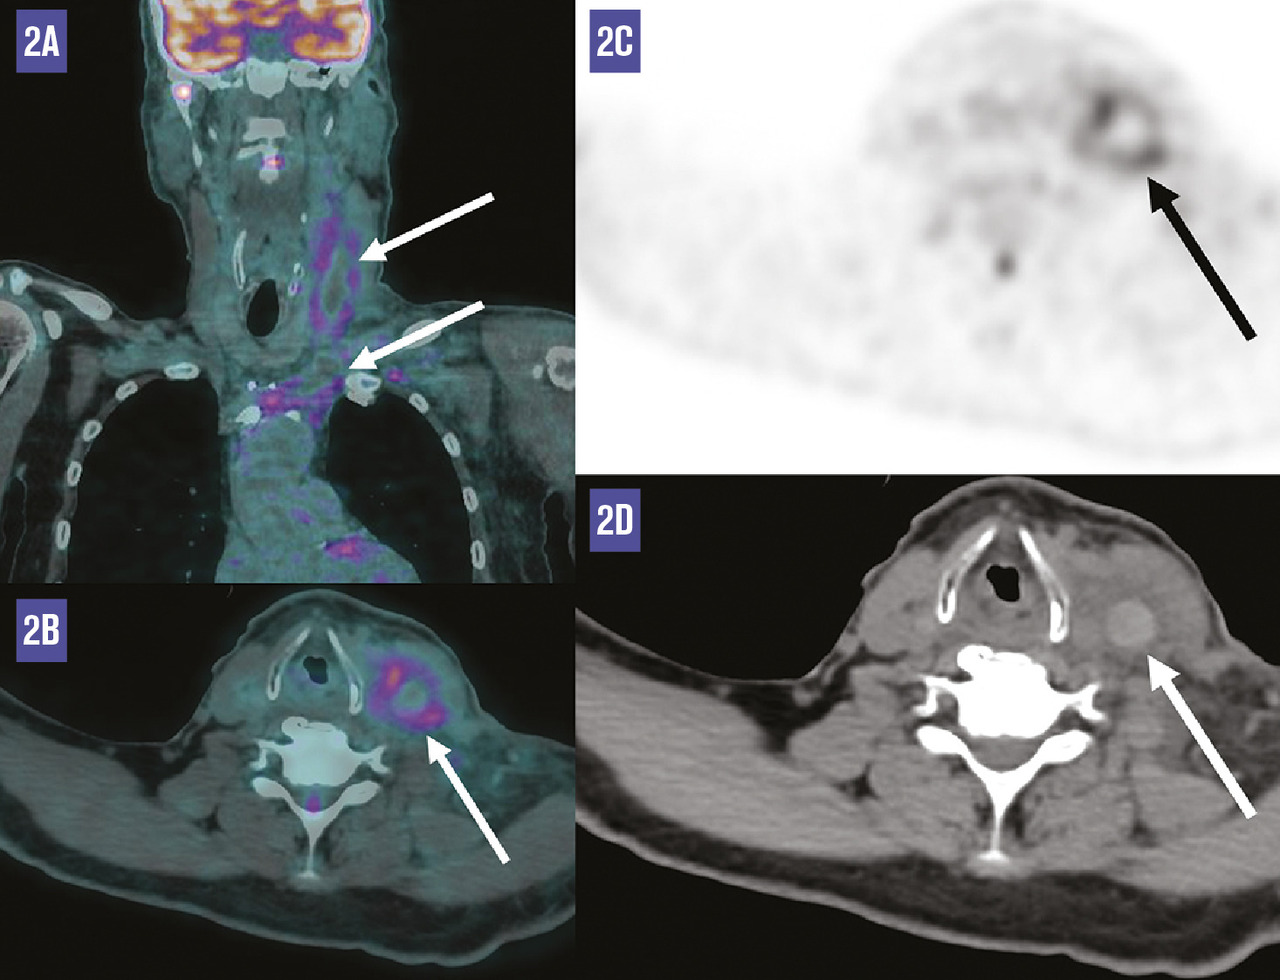

Ce patient de 63 ans était adressé pour bilan de douleurs abdomino-pelviennes associées à des adénomégalies cœliaques et lombo-aortiques dans un contexte d’altération de l’état général. La tomographie par émission de positons au fluorodésoxyglucose distinguait de multiples foyers hypermétaboliques ganglionnaires et osseux (fig. 1), ainsi qu’un hypermétabolisme intense du bas œsophage correspondant à un adénocarcinome. Il existait également un hypermétabolisme circonférentiel de la veine jugulaire interne gauche, s’étendant jusqu’au tronc veineux innominé, avec un aspect spontanément hyperdense au scanner (fig. 2). Ces anomalies étaient très évocatrices d’un thrombus. L’échographie veineuse en mode Doppler a confirmé ce diagnostic.